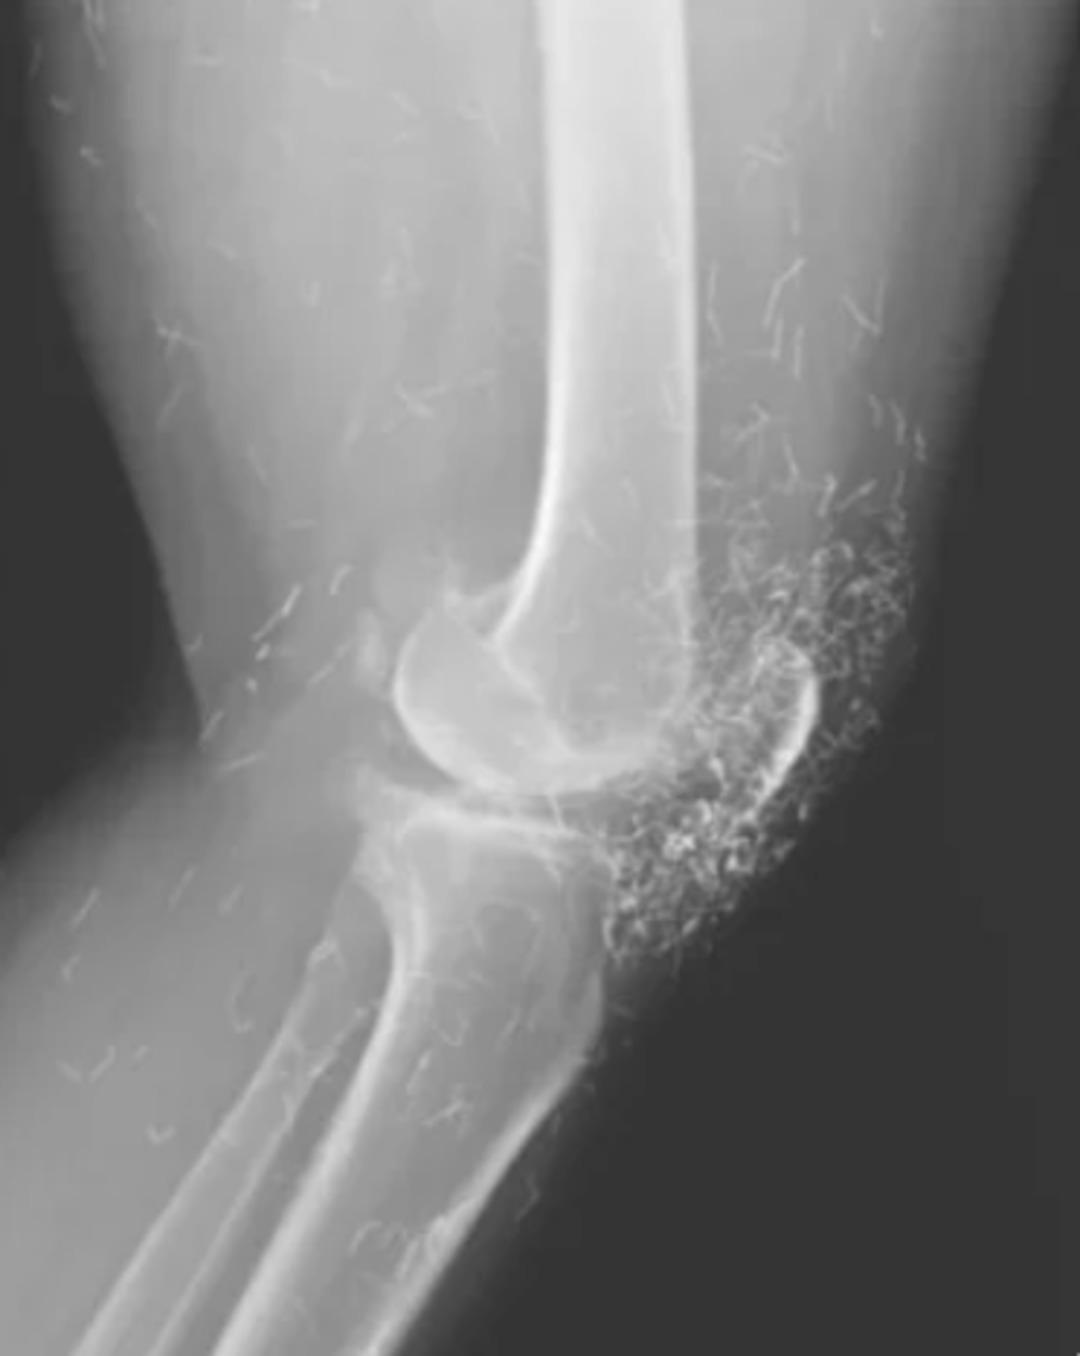

Güney Kore’de 65 yaşındaki bir kadın, şiddetli diz ağrısı şikâyetiyle hastaneye başvurdu. Yapılan röntgende yüzlerce altın iplik ile birlikte kemiklerde sertleşme, kalınlaşma ve mahmuz benzeri çıkıntılar tespit edildi.

Kadının daha önce kireçlenme (osteoartrit) tanısı aldığı, ancak ağrı kesici ve steroid tedavilerinden sonuç alamadığı öğrenildi. Mide rahatsızlığı nedeniyle ilaçları bırakan kadın, haftada birkaç kez “altın iplik akupunkturu” seanslarına katılmaya başladı.

Bu yöntemde, kısa ve steril altın iplikler deri altına yerleştirilerek sürekli uyarım amaçlanıyor. Doktorlar, ipliklerin vücutta bilinçli olarak bırakıldığını ancak zamanla yer değiştirebileceğini, kist oluşumu ve enfeksiyon gibi riskler taşıdığını belirtiyor.

Altın iplik akupunkturu, Asya’da kireçlenme ve iltihaplı romatizma tedavisinde yaygın kullanılıyor. Ancak uzmanlar, bu yöntemin etkinliğini destekleyen yeterli bilimsel kanıt olmadığını vurguluyor. Ayrıca bazı hastaların bu tedavi nedeniyle gerekli tıbbi müdahaleleri geciktirdiği uyarısı yapılıyor.

Daha önceki vakalarda, altın ipliklerin vücutta hareket ederek başka bölgelere ulaştığı ve enfeksiyona neden olduğu bildirildi. Ayrıca iplikler, röntgen ve MR gibi görüntüleme yöntemlerini zorlaştırabiliyor, hatta damar hasarına yol açma riski taşıyor.